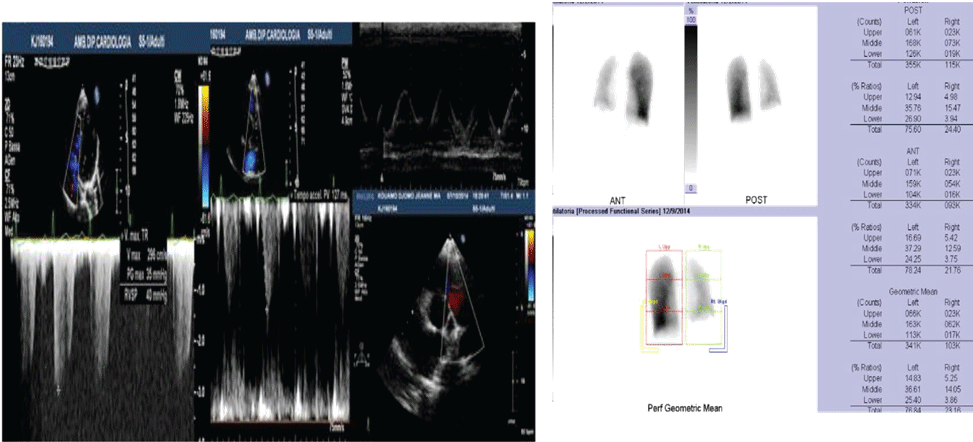

Figure 1: A) Case 1 echocardiogram showing high value of estimated systolic pulmonary pressure with sPAP 45 mmHg; B) Case 1 pulmonary scintigraphy showing low ventilation and no perfusion of the right lung. View Figure 1

A 21-year-old woman presented for a history of exertional dyspnoea and atypical chest pain. No history of allergies or tuberculosis. A chest X-ray showed asymmetry of the chest walls from a reduced expansion of the right lung caused by parenchymal loss and right deviation of the mediastinum and ipsilateral elevation of the diaphragm. Transthoracic echocardiogram showed high value of estimated systolic pulmonary pressure (sPAP 45 mmHg) with normal right ventricle (Figure 1A). Right pulmonary artery not viewable. Pulmonary scintigraphy releaved low ventilation with no perfusion of the right lung, with a normal left lung (Figure 1B). Spirometric test showed a restrictive-like dysfunctional pattern with mild reduction of DLCO, 6MWT: reduction in distance walked without desaturation. CPET: normal exercise tolerance with augmented heart rate response, VO2/HR 9.7 mL/beat; VE/VCO2 45; VO2max 31 ml/kg/min, compatible with pulmonary hypertension. Angio-CT scans of the chest showed right PAA with hypertrophic ipsilateral diaphragmatic and bronchial arteries; right lung hypoplasia with diffuse bronchiectasis area (Figure 2). A right heart catheterization confirmed a borderline precapillary pulmonary hypertension without vaso reactivity and right PAA (BOPAH; sPAP 40 mmHg, mPAP 22 mmHg, PVR 1.8 UW) (Figure 3). No specific therapy for PAH was started.

The chest X-ray scan showed left lung pneumonia. The echocardiogram confirmed the presence of a single branch originating from the main pulmonary trunk with a sPAP 60 mmHg; Actpo 80 msec. Microbiologic culture test and procalcitonin resulted negative. The patient was discharged with an indication to perform spirometric test with DLCO and pulmonary scintigraphy. Spirometry documented the normality of forced expiratory flows, lung volumes, the flow resistances and the DLCO (KCO) 98.6%. Cardio-pulmonary exercise test showed a VO2max of 35 ml/kg/min, VO2/HR 15 (ml/beat), VE/VCO2 37, VE/VO2 40 (Figure 4). The echocardiogram performed three months after, with stabilization of the bronchopneumonic framework, documented borderline values of sPAP (36 mmHg) and pulmonary outflow acceleration time (Actpo: 123 msec) (Figure 5A). The angio-CT and hrCT scans showed parenchymal consolidation of the left lung affecting all lobes. A diagnosis of right PAA with ipsilateral pulmonary hypoplasia and main pulmonary artery ectasia was done; hypertrophic systemic bronchial and intercostal collaterals (Figure 5B); Right heart catheterization showed normal values of pulmonary pressures (mPAP 15) and pulmonary vascular resistance (PVR 1.6). Some genetic disorders play an important role in lung morphogenesis, including mutations of BMPR2 and TTF-1 factor (thyroid transcription factor-1). Molecular analysis of the first case showed the presence mutations of BMPR2 as compound heterozygosity: Exon 3p Cys123Arg; Exon 8p Arg332X. These mutations have been described in the literature to be associated with the clinical phenotype of the proband and genetic investigation to the rest of the family was therefore recommended, but not yet performed.

Figure 5: A) Case 2 echocardiogram: Pulmonary artery trunk and Actpo from parasternal views; B) CT Scan. View Figure 5